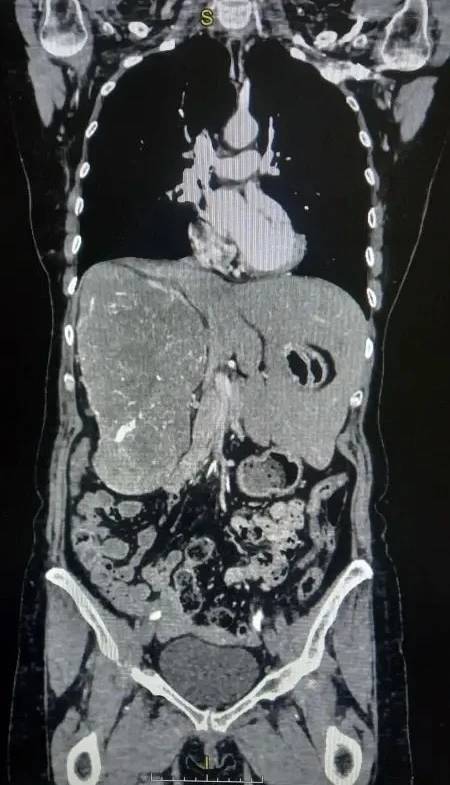

Как сообщает областной комитет здравоохранения, хирурги Волгоградского областного онкологического диспансера (ГБУЗ ВОКОД) провели редкую операцию на почке, где столкнулись с необычной анатомией: гигантская опухоль фактически сместила жизненно важные органы. Печень пациентки была полностью перемещена из правой стороны живота в левую.

Пациентка долго жаловалась на боли в пояснице и тяжесть в животе. Компьютерная томография с контрастированием показала, что опухоль почти полностью заняла правую половину брюшной полости и сместила печень. Правая почка почти не функционировала, о чем свидетельствовали результаты обследования. Размер опухоли составил 16,5х11,5х21,1 см.